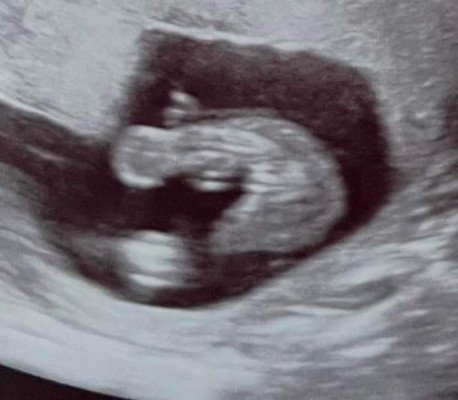

หญิงหรือชายคะ

หมอบอกว่าหญิง 60% ชาย40% อีแม่เอาภาพมาซูมดูใกล้ๆพอจะคอนเฟิร์มได้มั้ยคะ😂

น่าจะหญิงนะแม่ เป็นกลีบๆเลยอ่ะ

เห็นเป็นกลีบน่าจะ ญ นะคะ

เราว่าน่าจะหญิงนะคะ

น่าจะผู้หญิงนะคะ

คิดว่า ญ ค่าาา🙂

น่าจะ ญ นะคะ